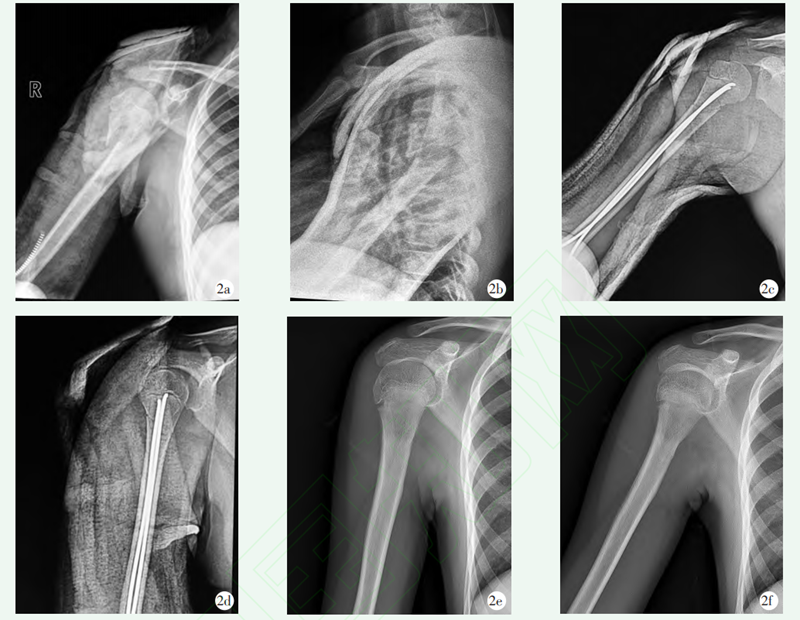

图2 患者,女,11岁,右肱骨近端骨折,行逆行弹性髓内钉固定

2a,2b:术前正侧位X线片示骨折明显移位,Neer Horowitz 3型;2c,2d:术后正侧位X线片示骨折复位满意,内固定位置良好;2e,2f:术后3年X线片示骨折愈合良好,颈干角满意